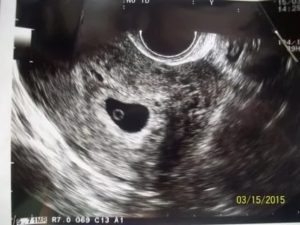

В 6 недель вынашивания эмбриона при проведении ультразвукового исследования на фоне утолщенного гиперэхогенного эндометрия определяется плодное яйцо. Оно представляет собой округлое или овальное анэхогенное образование с гиперэхогенным ободком.

Внутренний диаметр плодного яйца в этом сроке составляет порядка 22 миллиметров. Начиная с 5 недель беременности его размер увеличивается на 1-2 мм.

При несоответствии его размеров с предполагаемым акушерским сроком производят контрольное ультразвуковое исследование через 3-5 дней.

В плодном яйце уже должны визуализироваться эмбрион и желточный мешок. Располагаясь эксцентрично, они формируют изображение на мониторе в виде двойного пузырька. Желточный мешок определяется как округлое тонкостенное образование с анэхогенным содержимым внутри.

Его нормальная величина составляет 3-5 мм в диаметре. Функцией этого образования является питание эмбриона до тех пор, пока не сформируется плацента, которая займётся этим.